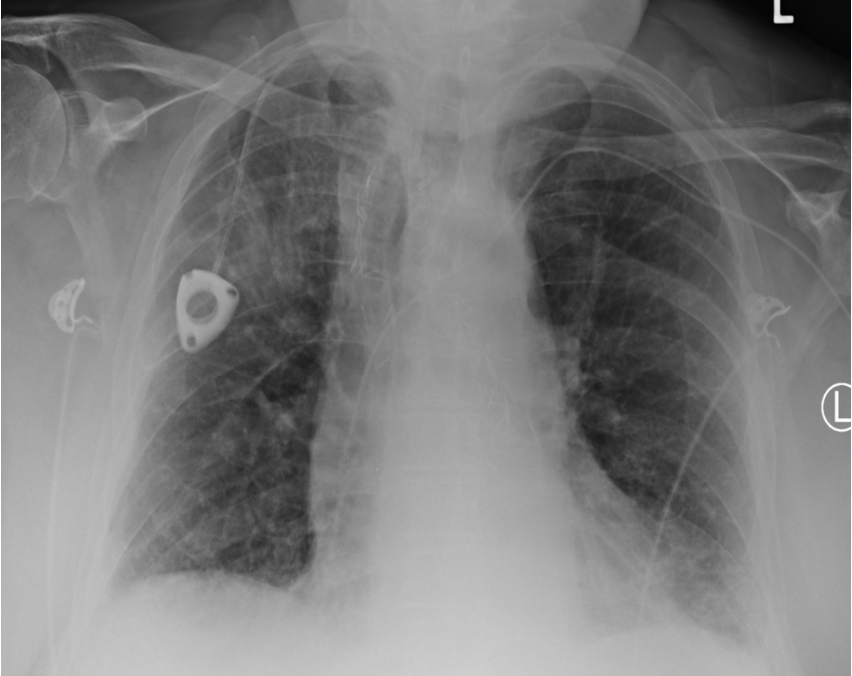

Slide 4

A pneumothorax is always a medical emergency until otherwise proven, as severe cases can be significantly life-threatening. Here is another example where the pneumothorax is in the top right (anatomically).